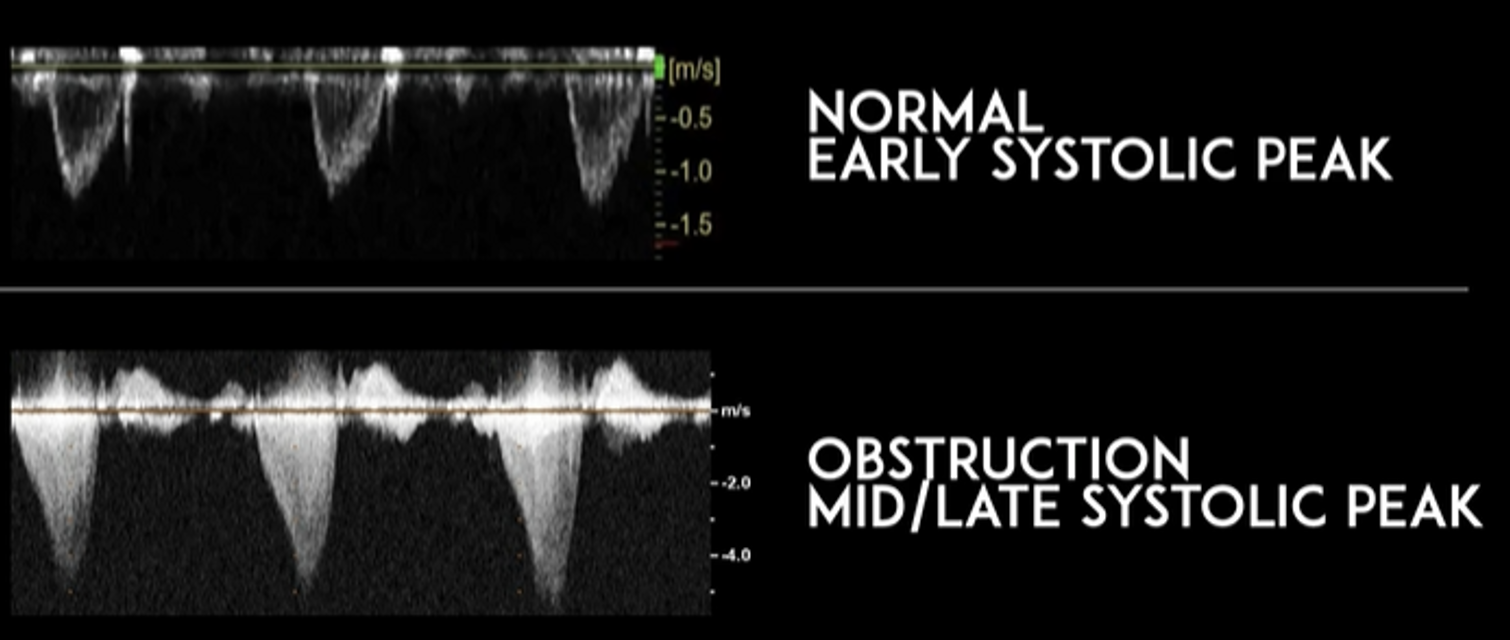

Finding #4: Left Ventricular Outflow Tract Obstruction (LVOTO)

• View: A5 View with Continuous Wave Doppler

• Doppler will show “dagger-like/shark fin” waveform (produced by a late systolic peak)

• Measure peak velocity to obtain a gradient

• Gradient > 30 mmHg indicates obstruction

• ⅓ of HCM patient will have a high gradient at rest

• ⅓ of HCM patients will have a high gradient with provocation (Valsalva, exercise, medication)

• ⅓ of HCM patients will have no obstruction

This image compares the waveforms of normal findings vs obstructive findings. Notice how the obstructive pattern appear like “daggers” or “shark fins.”